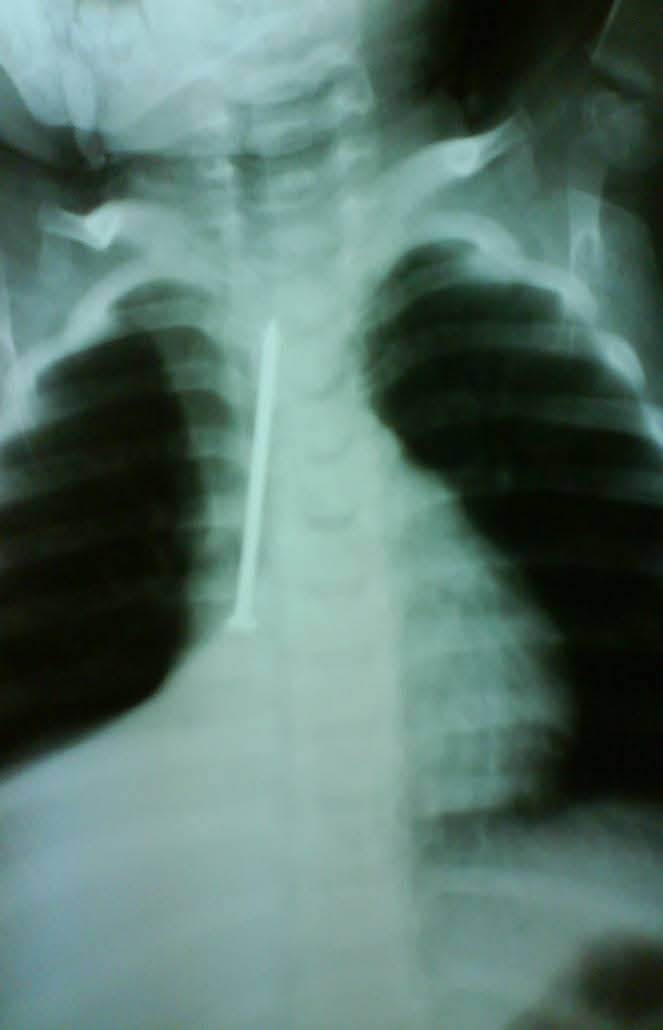

وأضاف قائلًا: "كانت الطفلة في حالة طبيعية تمامًا، تتنفس بشكل جيد ولا تعاني من أي صعوبة في البلع، لكن أمام إصرار الأم على أنها بحثت جيدًا في المنزل، قررت إجراء أشعة على صدر الطفلة، لتظهر المفاجأة الصادمة مسمار طويل يمتد بطول القفص الصدري تقريبًا".